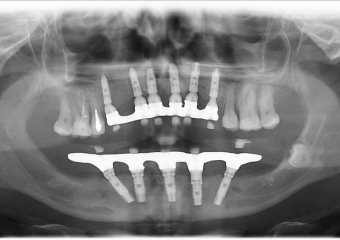

Raio - x Próteses Definitivas em Outubro de 2016  - Clínica Cliniface

Raio - x Próteses Definitivas em Outubro de 2016